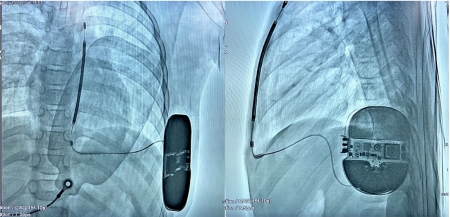

9岁的患儿南南(化名)因“意识丧失1次,心肺复苏术后1月”入院。刘启明教授带领心脏电生理团队,根据心电图长QT间期表现、注意力缺陷及多动障碍、并指等临床特点和CACN1C基因杂合变异,综合分析考虑诊断为国际罕见的Timothy综合征。12岁的患儿武武(化名)因“晕厥2次”入院,考虑为恶性心律失常幸存者,两人均有心脏性猝死二级预防指征。术前,刘启明教授带领团队与心血管外科、儿科、麻醉科等多学科深入讨论交流,确定了手术的必要性和可行。为了保证手术安全和顺利进行,心血管外科廖晓波教授、龚医博副教授术中给予了紧密配合。手术在全麻下进行,采用两切口植入(左腋中线第5-6肋切开约5cm切口,剑突左上缘1cm处切开长2cm切口),全皮下操作,无需穿深静脉,整个手术过程顺利。

心源性猝死是我国心血管病患者死亡的主要原因之一,而恶性室性心律失常是心源性猝死最常见的直接原因。及时识别并有效复律是预防这类患者发生心源性猝死的关键。S-ICD是在心源性猝死预防领域取得革命性突破的新技术,其优势在于整个系统完全埋藏于皮下,不需要经静脉途径放置除颤导线,通过皮下电极来采集信号,反映患者的真实心律,从而提供安全有效的复律治疗。同时也彻底避免了血管损伤的风险,降低了潜在的系统感染风险,保留静脉通路,避免经静脉导线植入或者拔除的相关并发症,为心源性猝死的高危患者提供了最新的治疗方案。